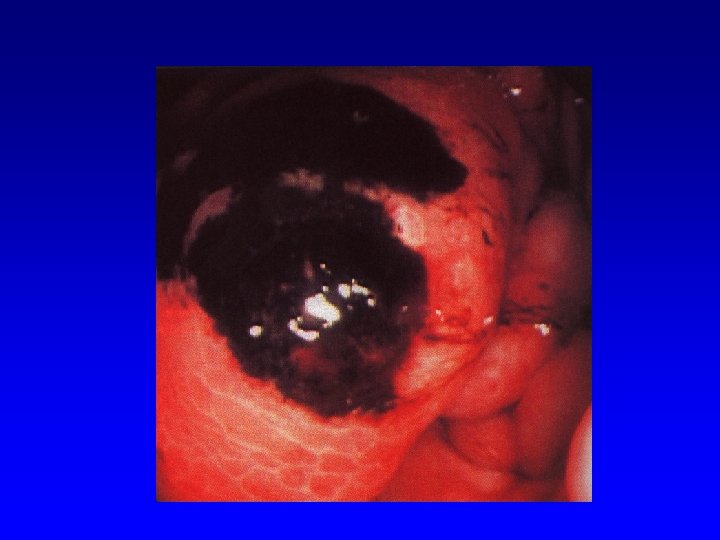

Clinical course of HEP C • • • ü ü LC in about 20 % patients with chronic HCV infection HCC annually in 1 -4 % patients with LC Progression to HCC depends on: age (more rapid progression in older persons) alcohol abuse HIV co-infection HBV co-infection